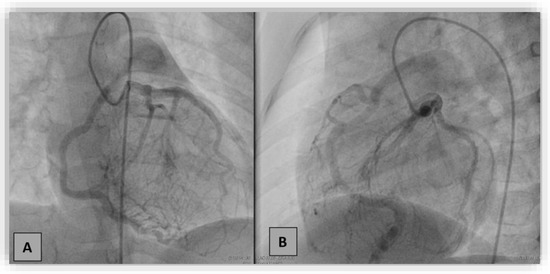

Anomalous origin of the right coronary artery (RCA) from the pulmonary artery, ARCAPA, is an extremely rare congenital heart disease. Only 200 cases were reported from 1885 to the present. Patients diagnosed with ARCAPA can be either asymptomatic or can experience symptoms, such as heart murmur, dyspnea, or angina, shortly after birth or around 40–60 years of life. Usually, those with isolated ARCAPA are diagnosed later in life compared to those who associate other structural cardiac defects. We report two cases of anomalous origin of the right coronary artery at the level of the pulmonary artery trunk (ARCAPA) that were diagnosed by invasive coronary angiography. Although asymptomatic, general recommendations suggest an early corrective intervention to prevent complications such as myocardial ischemia and cardiac dysfunction, which can lead to sudden cardiac death. Full article

Show Figures

Figure 1